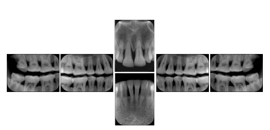

1. A patient in rural Canada visits a general ophthalmologist and is found to have diabetic macular edema. The general ophthalmologist would like to discuss the case with a retina specialist before performing laser surgery. A fluorescein angiogram is done with multiple retinal images taken in a timed series after an intravenous injection. The images along with a Structured Display are shared via a Health Information Exchange with a retina specialist in Calgary, who opens them using his Ophthalmology EMR software and consults via phone with the general ophthalmologist. Both physicians view the images in the same layout so the retina specialist can provide accurate guidance for treating the patient.

2. A patient in rural Iowa visits his primary care physician for management of diabetes. Three non-mydriatic (patient's eyes are not dilated) photographs are taken of the back of each eye, and forwarded electronically along with a Structured Display to an ophthalmologist in Iowa City. The ophthalmologist reads the photos in an agreed upon layout so there is no mistake about what portion of which eye is being viewed. The ophthalmologist is able to tell the primary care physician that his patient does not need to come to Iowa City for face to face ophthalmologic care, but that there is a particular view of the left eye that should be photographed again in 6 months.

Ophthalmic Retinal Study Structured Display

Figure OO-3. Ophthalmic Retinal Study Structured Display